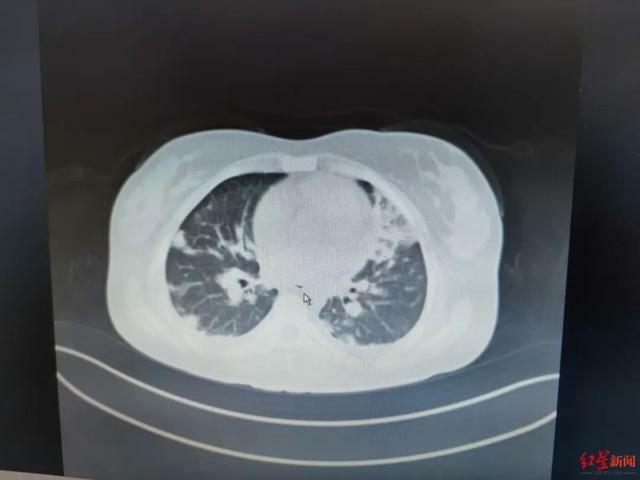

患者肺部炎症明顯,醫院供圖

臨床上,感染壞死梭桿菌最初表現可能就是普通的上呼吸道感染症狀,比如咽喉疼痛、急性咽炎、化膿性扁桃體炎等,然後經血流播散至其他器官,則可引起敗血症、膿毒血症和轉移性膿腫,最常見的是感染肺部引起的肺膿腫、肺栓塞、胸腔積液、氣胸等。早期不易確診,如不及時救治,死亡率達60%。